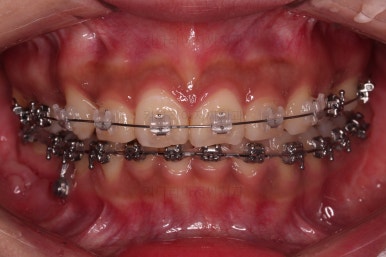

4. 마무리

할 수 있는 부분과 수용한 부분을 구분해서 환자분과 적절히 치료계획을 타협하고요. 치료를 마무리합니다.

가지런한 느낌 좋고요.

교합도 잘 맞고 이 뽑은 자리도 틈이 없으며 사랑니 당겨온 자리도 틈새 없이 잘 마무리가 되었네요.

다만 앞니가 예전에 부러져 있어서 형태저긍로 조금 부족하긴 했지만 나쁘지 않았습니다.